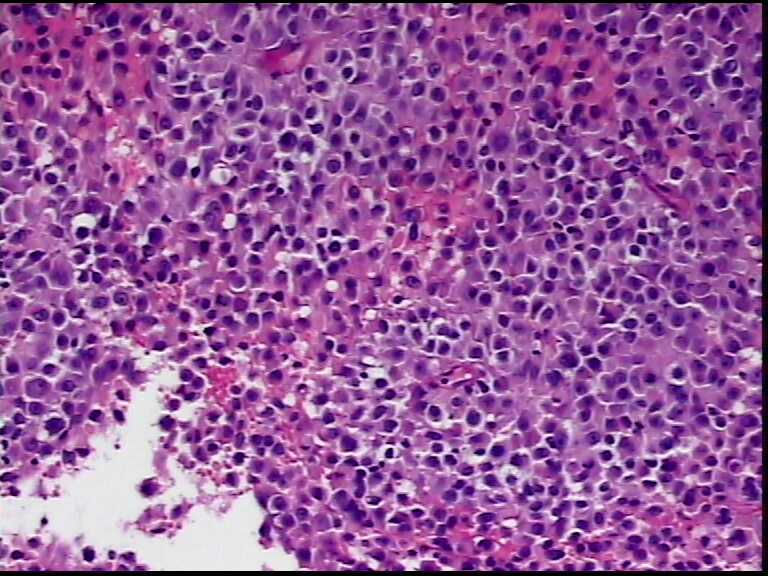

患者男性,34岁,临床没给提供,该患者梅毒阳性

颌下淋巴结肿大,送检肿物直径2.5cm,切面灰粉色,质地嫩,先做了个LCA瘤细胞阴性